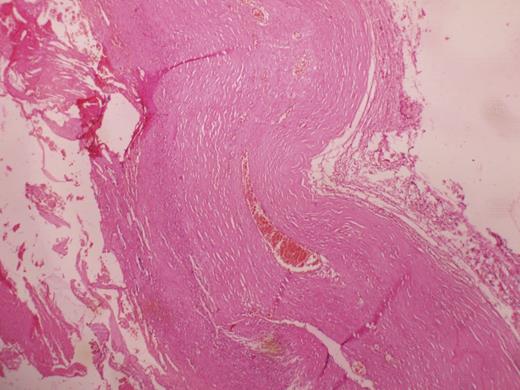

Histopathological slide showing the absence of lining epithelium.

The wall of a pseudocyst is composed of dense fibrous tissue with no epithelial lining and occasionally contains hemosiderin. To our knowledge, serum CA 19-9 levels are high in most true cysts but are rarely high in hemmorhagic pseudocysts because of the absence of epithelial lining [4]. CA 19-9 levels were raised in one of our cases.